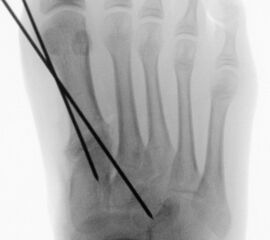

Werden komplette Osteotomien an den Zehen durchgeführt, fädeln wir die Osteotomien mit einem 1.2 oder 1.4 mm Kirschner-Draht auf, damit die einzelnen Fragmente nicht verkippen (Abb. 22).

Abb. 22 a-d: Präoperative Klauenzehen beim Jugendlichen in zwei Ansichten (a-b) und postoperative Auffädelung mit Kirschner-Drähten linker und rechter Fuß (c-d).

Zum Lesen der Bildbeschreibung und zur Vollansicht bitte die Bilder anklicken. Bilder: A. Helmers.